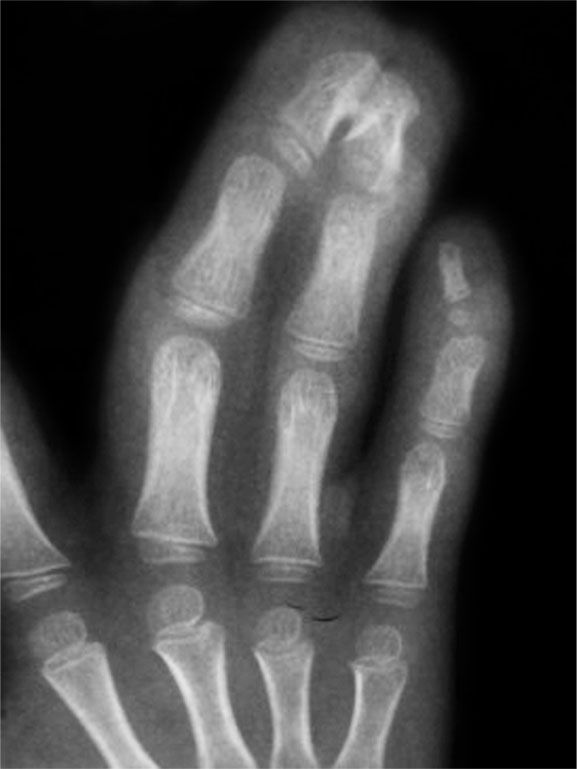

图1-2-26 Apert 综合征指骨末端骨性融合